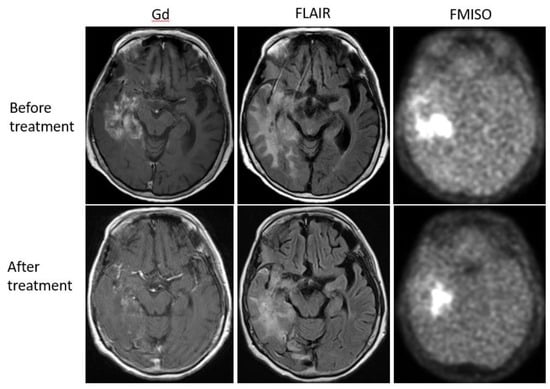

Figure 6. A 68-year-old patient with anaplastic astrocytoma showed a strong uptake of FMISO before the bevacizumab treatment (upper row). After the treatment, MRI showed shrinkage of the tumor, but FMISO uptake was still observed (lower row). The patient was considered a ‘MRI-only responder’.

Bevacizumab is a recombinant humanized monoclonal antibody that blocks angiogenesis by inhibiting vascular endothelial growth factor A (VEGF-A) [58]. Although bevacizumab failed to prolong the overall survival of patients with primary glioblastoma [59,60], it was effective in some populations of recurrent glioma patients. In our retrospective study, we investigated whether FMISO PET has the potential to distinguish responders to bevacizumab from non-responders [61]. Eighteen patients with recurrent glioma underwent bevacizumab treatment. We compared the patients’ pre-and post-MRI and FMISO PET to classify them as (1) MRI-FMISO double responders (n = 9, Figure 5), (2) MRI-only responders (n = 5, Figure 6), and (3) non-responders (n = 4, Figure 7). There were no FMISO-only responders. The survival analysis demonstrated that the MRI-FMISO double responders had significantly longer overall survival than the other patients, whereas no significant difference was observed between the MRI-only responders and the non-responders. We thus concluded that recurrent gliomas with decreasing FMISO accumulation after short-term bevacizumab application could derive a survival benefit from the treatment.